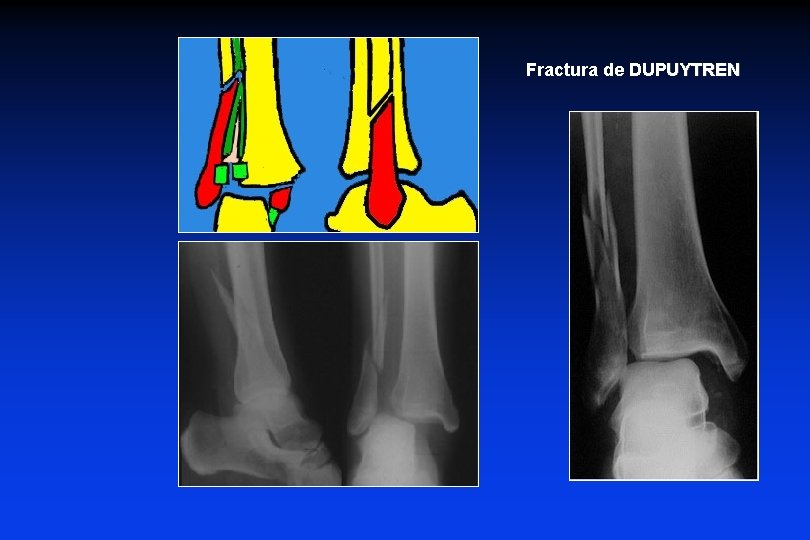

3 - FRACTURAS en ROTACION EXTERNA supra-ligamentarias (en abducción) Estadio 1: Fractura del maléolo interno (o LLI) 2: Ruptura del ligamento peroneo-tibial anterior, diastasis + 3: Fractura del peroné, oblicua de abajo hacia posterior (alta o baja) 4: Ruptura del ligamento peroneo-tibial post, membrana inter-ósea, diastasis +++ Fractura de DUPUYTREN

Fractura de DUPUYTREN

• El peroné puede fracturarse en el tercio proximal (fractura de MAISONNEUVE)